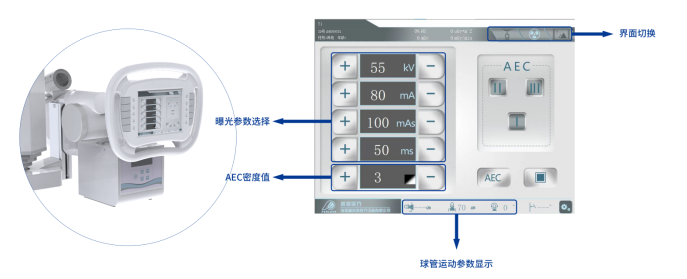

● 曝光前的預設均可近臺設置

智能觸控系統通過屏幕操作,可以在進行曝光工作檢查前對數據進行調整。

● 信息雙向傳輸

觸控屏與工作臺信息同步,支持在任意一側登記病人信息。